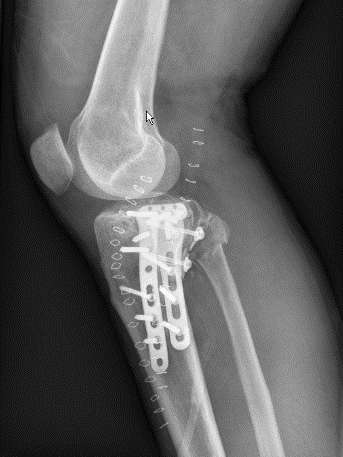

4、图8-9 术后X片见骨折复位及内固定满意